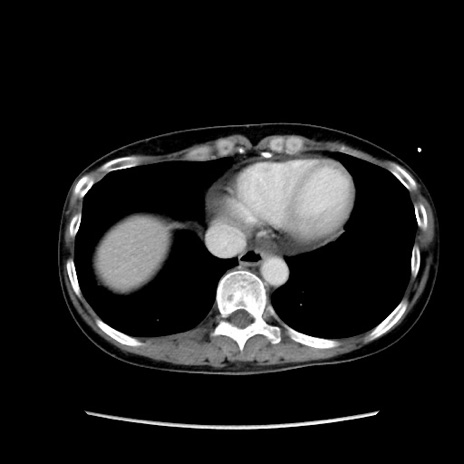

症例32(横断像)

【症例】40歳代 女性

【主訴】上腹部痛、嘔気・嘔吐

【現病歴】約9時間前頃から急に上腹部痛、嘔気、嘔吐が出現。改善しないため救急要請。

【既往歴】子宮頚癌(広汎子宮全摘術、放射線療法)、腸閉塞

【身体所見】腹部:平坦、軟、腸雑音亢進、上腹部を中心に腹部全体に圧痛あり。

【データ】WBC 8400、CRP 0.03